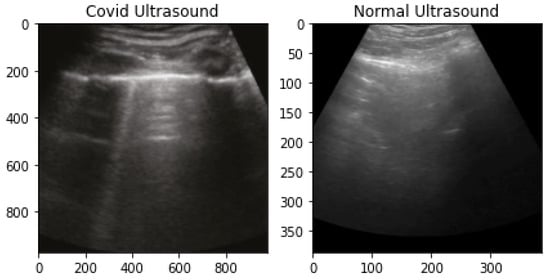

The Public LUS dataset (POCUS) is used in this research; it is compiled by Born et al. [56]. POCUS dataset contains videos and images of two types, convex and linear. Convex and linear are two types of transducers, which are used to generate ultrasound. At the time of this study, it contained in total 162 videos of convex probe (46 pandemic-infected, 46 bacterial pneumonia, 64 healthy and three viral pneumonia). It had twenty videos of linear probe (6 pandemic-infected, 2 bacterial, 9 healthy, 3 viral pneumonia). The butterfly dataset was not considered in this study. The total number of images of the convex probe is 53, including 18 pandemic-infected, 20 pneumonia and 15 healthy LUS images. There are 6 images of the linear probe, with 4 pandemic-infected and 2 pneumonia images. The samples of both normal and pandemic-infected lung ultrasounds are shown in Figure 4.

Figure 4.

Covid-infected and Normal Lung Ultrasound Data Samples.